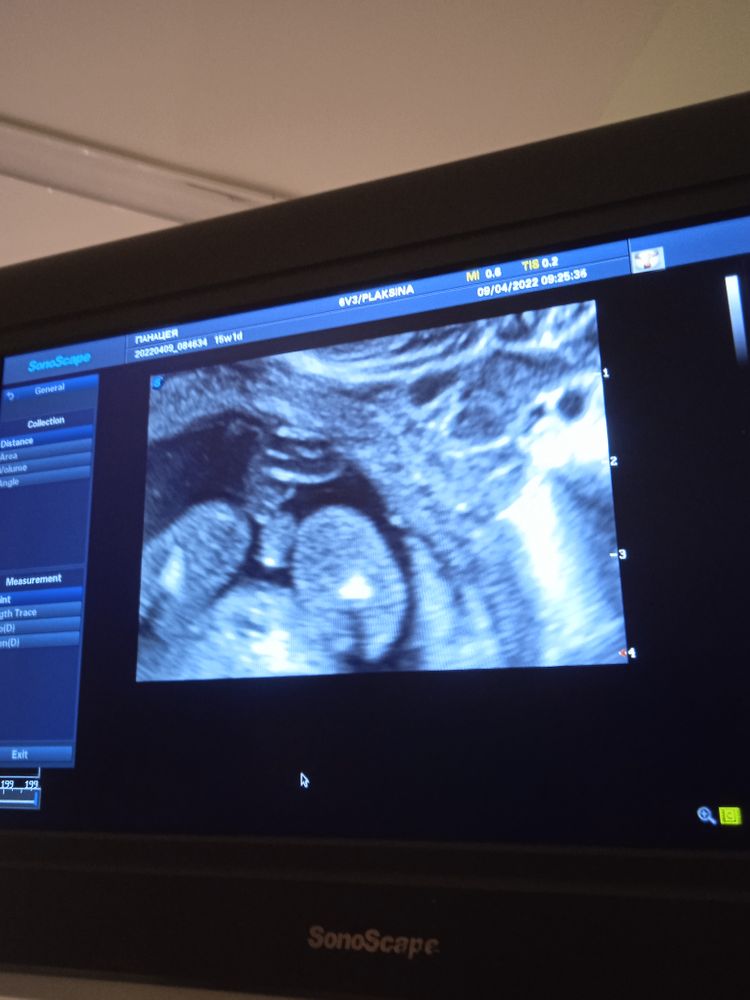

Юлия Sonnце, Изображение 15 недель и 1 день, мальчик же?

Изображение Сказала узист, что это мошонка... Юлия Sonnце,

Екатерина Шайхутдинова, на этом снимке больше на пуповину похоже... Но узисту, наверное, виднее. А так, у Вас же скоро скрининг должен быть, если ориентироваться на срок. Там уже точно скажут😊